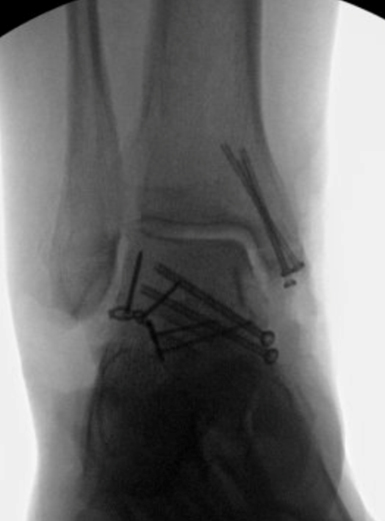

TOTAL ANKLE REPLACEMENT :: ORIF CALCANEUS :: ORIF ANKLE FRACTURE DISLOCATION :: COMPLEX BUNION AND LESSER TOE CORRECTION :: TALUS FRACTURE -1 :: TALUS FRACTURE -2 :: LISFRANC REPAIR :: COMPLEX TRIPLE ARTHRODESIS 1 :: COMPLEX TRIPLE ARTHRODESIS 2 :: MINIMALLY INVASIVE BUNION REPAIR 1 :: MINIMALLY INVASIVE BUNION REPAIR 2 :: ARTHROSCOPIC CARTILAGE REPAIR :: TENEX SPUR DEBRIDEMENT :: Haglunds Debridement and Achilles Repair